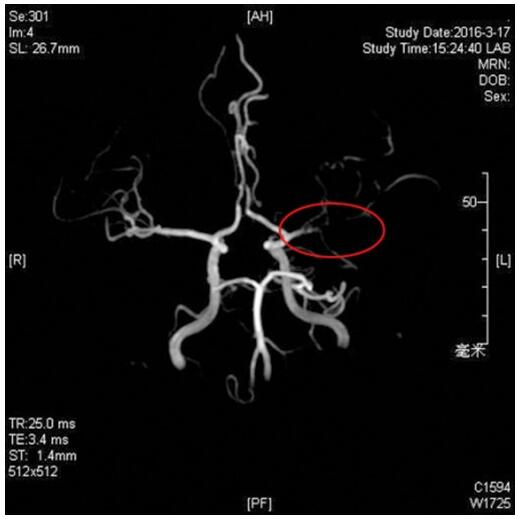

术前磁共振血管成像:左侧大脑中动脉闭塞。